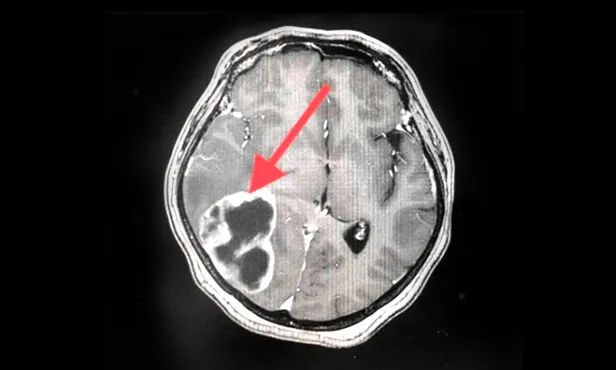

▲ 剛?cè)朐簳r(shí)病灶影像

▲ 完成穿刺,黑色囊液被順利引流

▲ 經(jīng)復(fù)查,病灶較前明顯縮小

按照腫瘤復(fù)查的標(biāo)準(zhǔn),復(fù)查影像顯示王女士顱內(nèi)病灶相較于來院時(shí)明顯縮小。家屬為此特意向陳琦主任致謝,并對(duì)醫(yī)院的治療和服務(wù)表達(dá)了充分肯定。